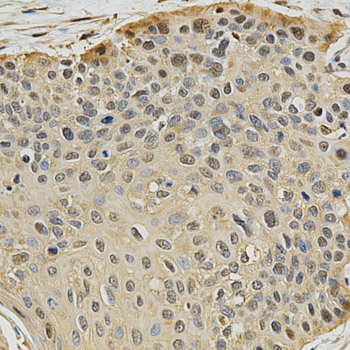

Immunohistochemistry of paraffin-embedded human esophageal cancer using PSMB9 antibody at dilution of 1:200 (x400 lens).